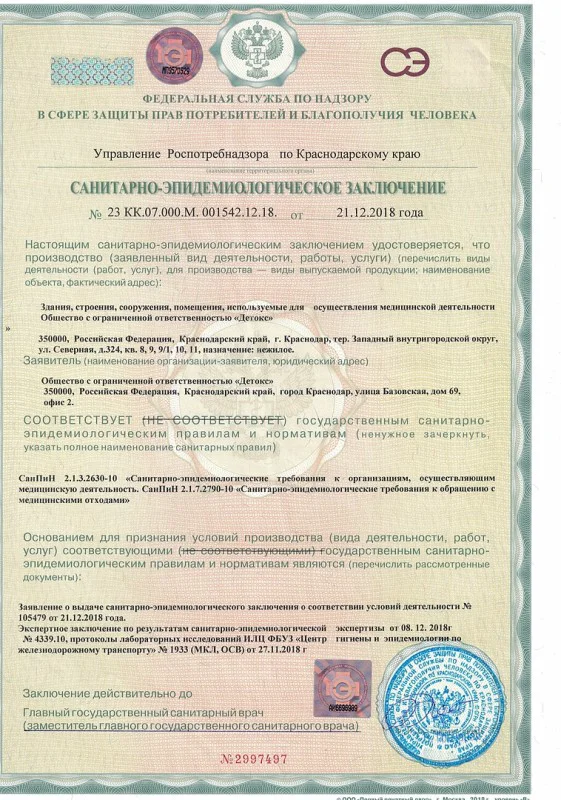

Лицензия на осуществление медицинской деятельности

Лицензия на осуществление медицинской деятельности

Лицензия на осуществление медицинской деятельности

Лицензия на осуществление медицинской деятельности

Лицензия на осуществление медицинской деятельности

Лицензия на осуществление медицинской деятельности

Лицензия на осуществление медицинской деятельности

Лицензия на осуществление медицинской деятельности